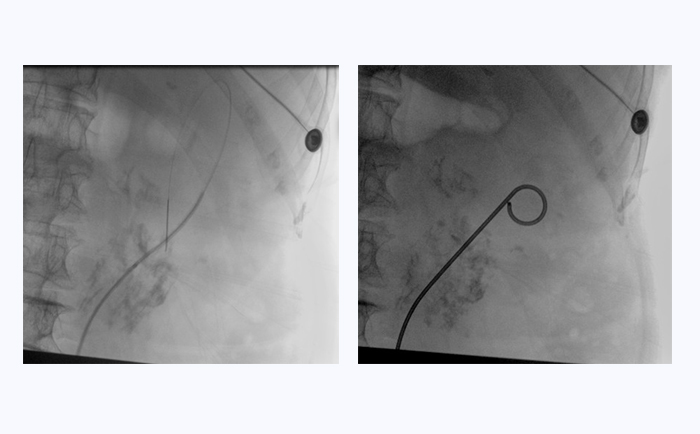

患者采用結石位進行該手術。全麻后,操作輸尿管鏡從尿道進入膀胱,通過鏡下觀察,找到輸尿管開口。此時,在普愛醫療大平板一體式C形臂透視引導下,穿入導絲,到達腎盂并確認位置,同時配合輸尿管鏡,找到狹窄部位。接下來,同樣在透視引導下,沿導絲插入雙J管支架,當支架兩端到達相應位置后,抽出導絲和輸尿管鏡,完成手術。

普愛醫療大平板一體式C形臂臨床圖像

大視野:一次呈現更多細節